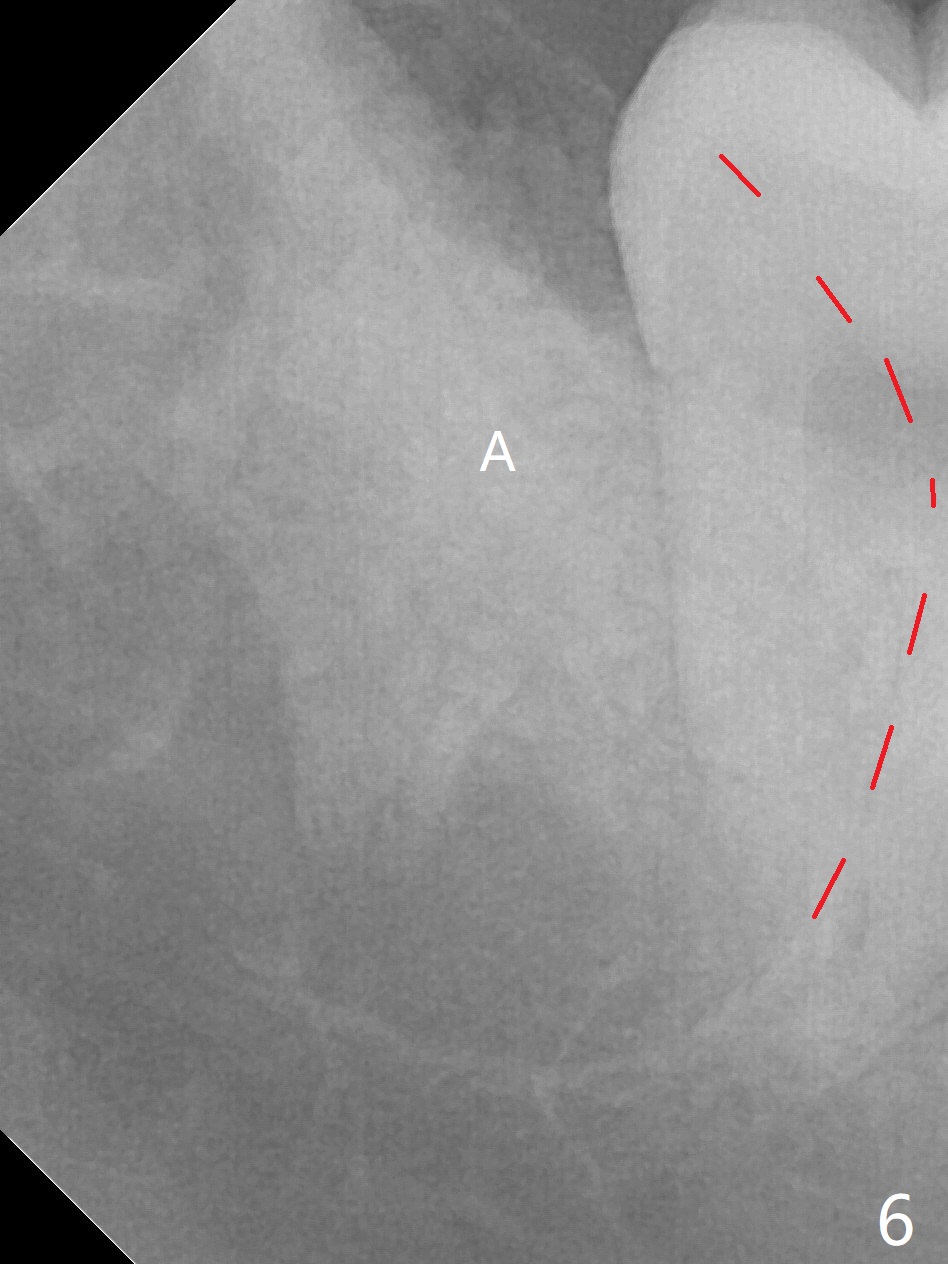

A 17-year-old man will return for extraction of 4 of the 3rd molars (Fig.1). Since the distobuccal surface of the tooth #31 may lack the bone (Fig.2 *), half of Augma will be placed in the distal portion of the sockets of #17 and 32, while allograft in the mesial one. Take PAs immediately post extraction to determine bony defects of the lower 3rd molars. Insert a piece of 2x2 gauze into the socket immediately post extraction. If hemorrhage is severe because of closeness between the mesial roots of the lower 3rd molars and the Inferior Alveolar Canal (Fig.2,3 red dashed line) after removal of the gauze, insert a half piece of Collagen Plug or more into the socket. If the latter is effective in hemostasis, Augma will be not applied, but allograft will be used, followed by Collagen Plug on the top of the allograft and sutures. Prepare both 4-0 and 5-0 ones. In fact the patient chooses to have 2 of the 3rd molars to be extracted. The extraction at #32 turns out to be extremely difficult with numerous sectioning because the crown of #32 is embedded into the distolingual surface of the fused conical roots of #31 (Fig.4,5). After insertion of a whole piece of Osteogen plug (Fig.7 O) into the root portion of the socket, Bond Apatite (1 cc) is pressed into the coronal portion of the socket (Fig.6 A). Due to oozing, the cement does not seem to be set completely. One third piece of Collagen plug is placed on the top of the cement before 4-0 Chromic gut suturing tightly. CBCT will be taken for better treatment approach prior to #17 extraction. Return to Plug Augma Xin Wei, DDS, PhD, MS 1st edition 10/06/2019, last revision 12/28/2019